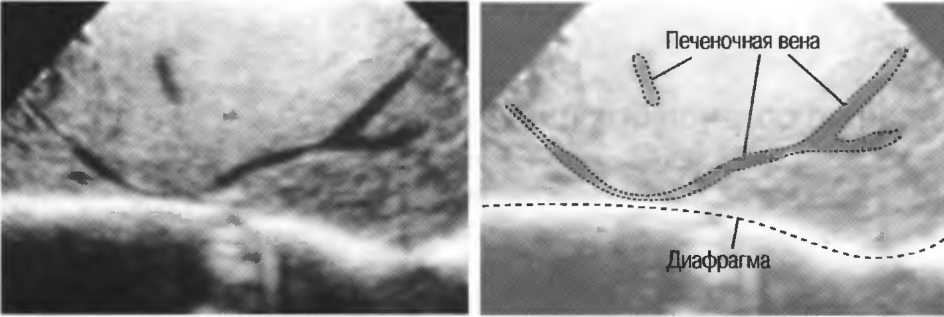

- Печеночные вены диаметром всего 3 мм должны визуализироваться при сканировании под углом 45° к поверхности нормальной печени (рис. 25).

Рис.25. Аппарат хорошего качества должен позволять визуализировать печеночные вены диаметром 3 мм. Этот тест может регулярно использоваться для контроля качества изображения.